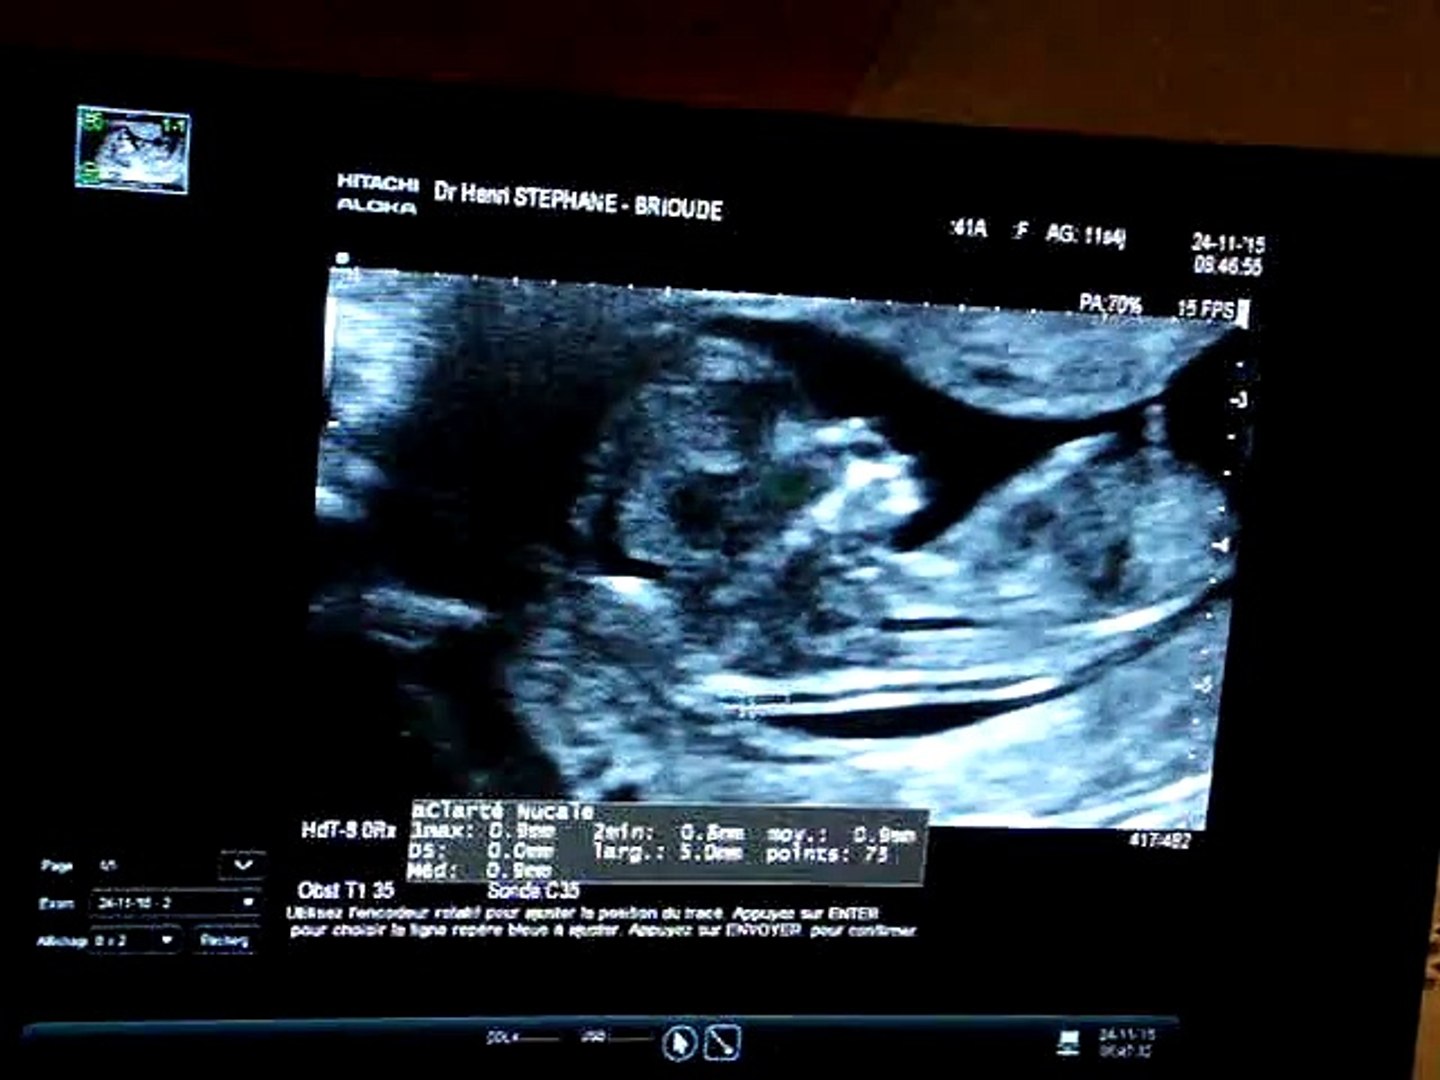

Elle est parfois précédée d'une avantpremière échographie pour rassurer sur un risque deRetrouvez toutes les anecdotes de ce 7ème mois de grossesse sur mon blog http//wwwbloghappychantillycom/magrossessede6a7moisRendezvous avec nos 2 petits bébés d'amour11ème semaine de grossèsse

Echographie bebe 3 mois grossesse- Cela correspond aux 9, 10 et 11eme semaines de grossesse (soit environ 3 mois de grossesse) Cette échographie dure environ 30 minutes Elle permet d'examiner la tête, le thorax, les membres, le ventre, les différents organes et notamment le cœur du fœtus afin de s'assurer de la vitalité fœtaleTrois échographies de dépistage sont recommandées aux femmes enceintes à chaque trimestre de la grossesse Elles permettent de suivre l'évolution et le bon développement du futur bébé tout au long de ces neuf mois

Bonjour, voilà mon premier film, je suis un petit garçon mais je ne sais pas encore comment je m'appelle Je ne suis pas encore prêt pour le festival de Cann Première écho, les détails La première échographie, dite de « morphologie embryonnaire », est réalisée entre la 11e et la 13e semaine d'aménorrhée (décompte à partir du 1er jour des dernières règles), soit la 9 e et 11 e semaine de grossesse;C est surement un peu tôt car je n etais pas tout a fait à 12sa La LLC est de 55,3